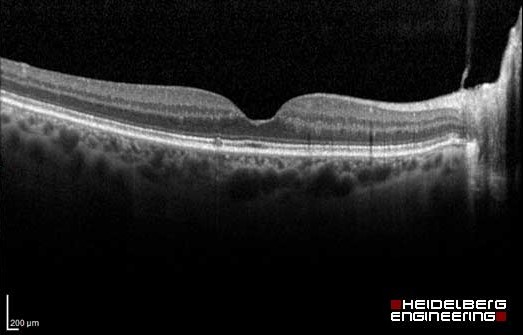

At Raison Opticians we offer the latest in eye scanning. The Optical Coherence Tomographer (OCT), photographs and scans the back of the eye, detecting small changes, through the layers of the retina – this allows us to spot abnormalities up to 5 years before a traditional test.

The OCT examination is completely non-invasive and painless. Nothing touches your eye at all. It only takes a few seconds, after the Optometrist has taken the scans, they will explain and interpret the results for you.